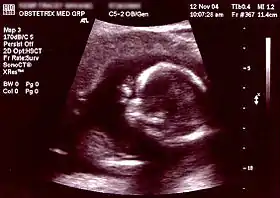

![]() صورة صدى توليدية لجنين في الأسبوع 16. الدائرة المستنيرة في النصف الأيمن هي الرأس، الذي يتجه يسارًا. من المعالم الواضحة الناصية التي هي في اتجاه الساعة 10، والأذن اليسرى التي هي على الساعة 7، واليد اليمنى التي تغطي العينين على الساعة 9. | |